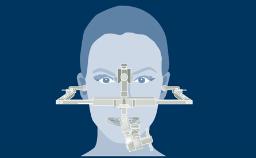

A substituição dentária por implantes oferece um tremendo benefício para os pacientes. Para garantir o sucesso a longo prazo da terapia com implantes, é importante entender o ambiente biológico complexo presente nos implantes. Os implantes são dispositivos biomédicos que existem sob demandas funcionais em um ambiente moldado pelas interações biológicas entre o biofilme microbiano e a resposta imune. A manutenção da saúde do tecido peri-implantar é, portanto, fundamental para a sobrevivência a longo prazo, o sucesso e o benefício da terapia com implante para o paciente.

- reconhecer as características anatômicas dos tecidos moles peri-implantares saudáveis